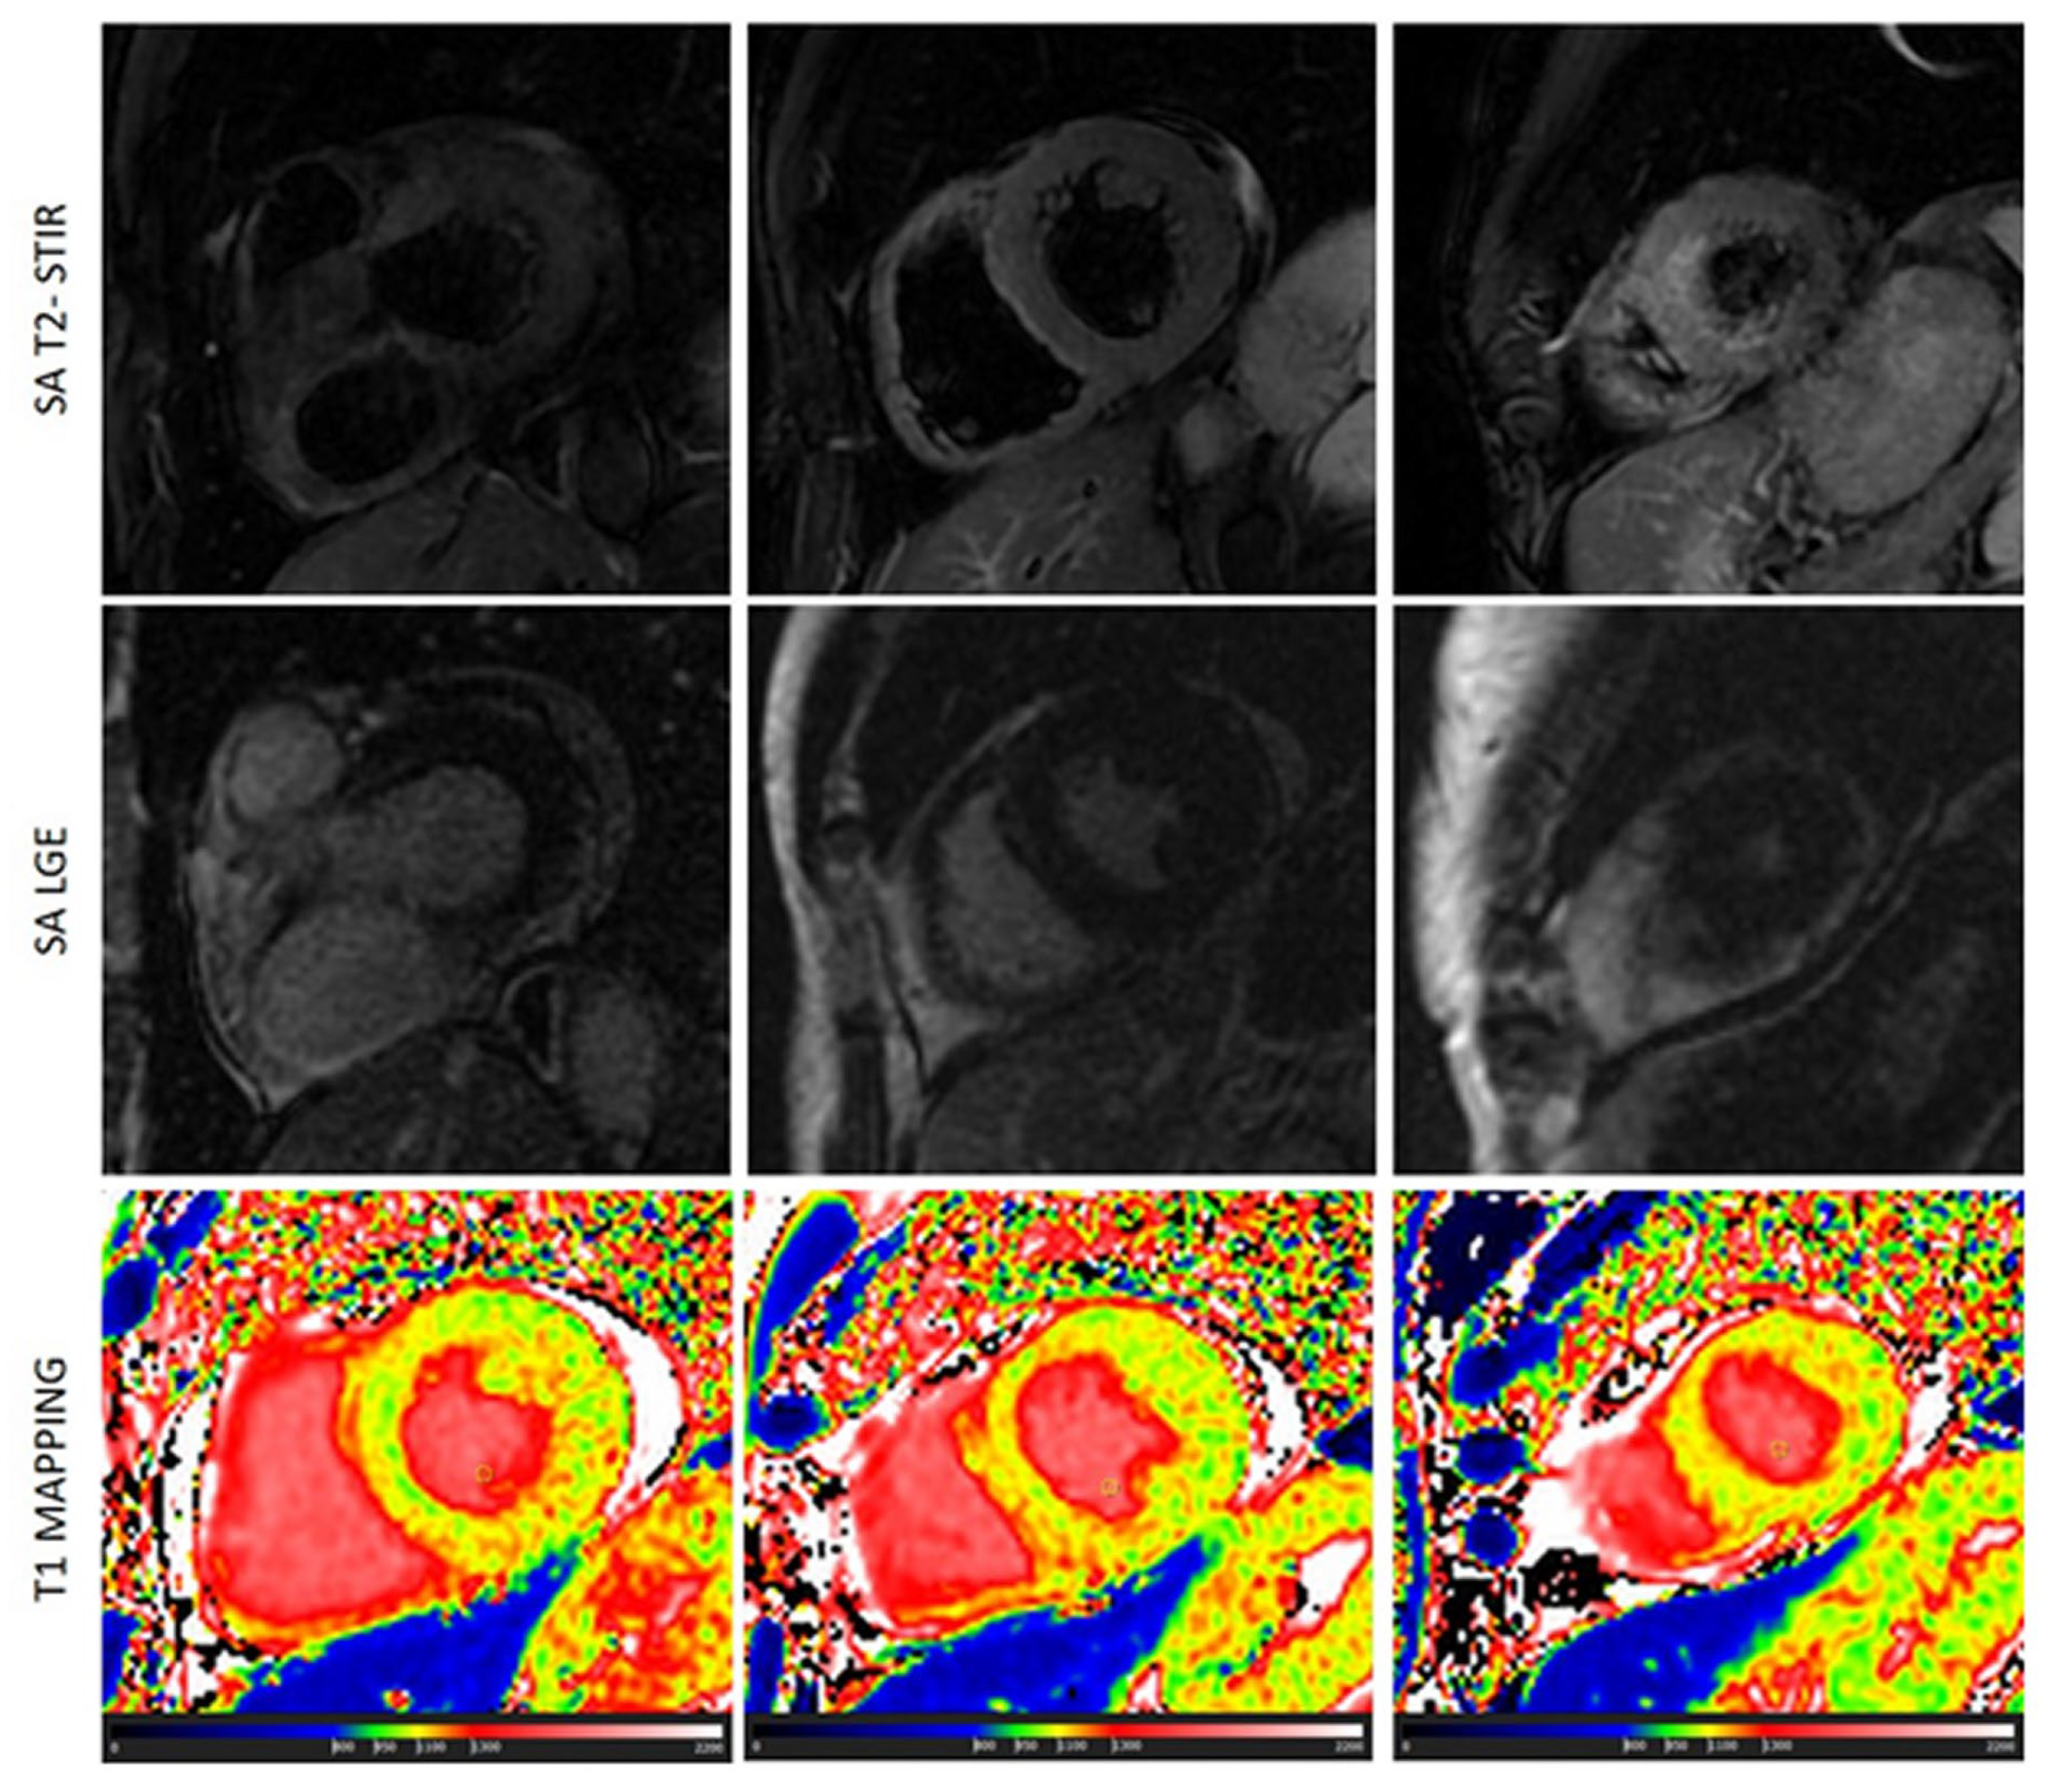

Scleroderma is usually associated with edema and microscopic fibrosis (figure 4). Both of them may present with a diffuse, non-regional, distribution. Microscopic fibrosis could be not detected by LGE [5,23]. The identification of diffuse edema, as well, is very challenging using conventional, qualitative, T2-STIR pulse sequence because of lack of comparison with “normal” myocardium. In this setting, native T1 and ECV evaluation could be very useful. Native T1 was abnormal in all the patients with these conditions and an additive role of T1 mapping over conventional techniques was found in 47% of cases of scleroderma. T1 was found positive in a significant higher percentage of cases of scleroderma than LGE\T2-STIR.

Figure 4. a case of scleroderma with negative LGE and T2-STIR image but with a diffuse increase of myocardial native T1 (normal range of T1 in green).